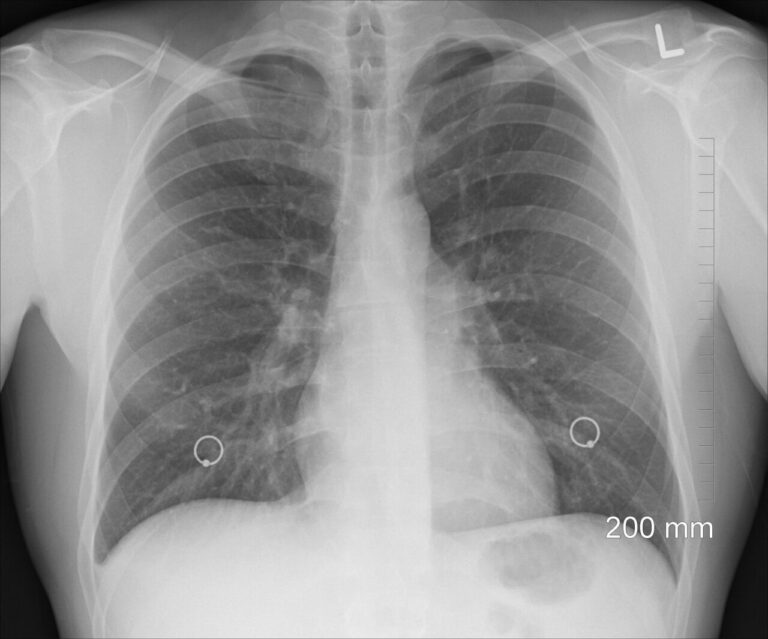

Zespół z University of Hull donosi o odkryciu związanym z wszechobecnym plastikiem. Naukowcy twierdzą, że po raz pierwszy wykryli cząstki mikroplastiku w płucach żywych osób.

Mikroplastik to niewielkie, mikroskopijne cząstki tworzyw, powstające przy naturalnym rozpadzie czy ścieraniu różnego rodzaju odpadów i przedmiotów codziennego użytku. Jak pokazują kolejne badania, cząstki te zanieczyszczają już niemal każdy element środowiska naturalnego i otoczenia człowieka. W 11 spośród 13 próbek tkanek płuc naukowcy znaleźli 39 cząstek mikroplastiku.

„Mikroplastik znajdowano już w próbkach pochodzących z autopsji. Tym razem jest to pierwsze, znaczące badanie, wskazujące na obecność plastiku w płucach żywych ludzi” – podkreśla Laura Sadofsky, główna autorka pracy opublikowanej w piśmie „Science of the Total Environment”.

„Pokazuje ono również, że cząstki te obecne są w dolnych częściach płuc. Kanaliki w płucach są bardzo cienkie, więc nikt nie spodziewał się, że plastikowe cząstki mogą się przez nie przedostać. Ewidentnie jednak tam są” – mówi ekspertka.

Próbki płuc zostały pobrane od pacjentów w czasie rutynowych zabiegów chirurgicznych.

Najwięcej było cząstek polietylenu i nylonu. W próbkach z górnych partii płuc badacze wykryli w sumie 0,23 cząstki na gram tkanki, ze środkowych części – 0,33, a z dolnych – 1,65. Znacznie więcej cząstek znajdowało się w płucach mężczyzn, niż kobiet. Cząstki miały rozmiary od 12 do prawie 2,5 tys. mikrometrów.

„Nie spodziewaliśmy się największej liczby cząstek w dolnych rejonach płuc, ani cząstek o takich rozmiarach. To zaskakujące, ponieważ przewody transportujące powietrze są węższe w dole płuc. Spodziewalibyśmy się więc, że cząstki o takiej wielkości zostaną zatrzymane, zanim dostaną się głębiej” – wyjaśnia dr Sadofsky.